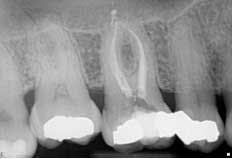

Radiographic interpretation showed the maxillary sinus, which appeared to be superimposed over the apex of teeth Nos. 2 through 4. In the radiograph No. 2 showed a shallow occlusal radiopaque restoration consistent with the appearance of amalgam. The mesial aspect of the tooth was visible with the mesiobuccal root showing. A radiopaque structure appeared to be within the chamber consistent with the appearance of a pulp stone. An apparent widening of the PDL at the apex of the tooth was visible. Tooth No. 3 showed a radiopaque MO restoration within 2 mm of the pulp chamber. The tooth appeared to exhibit three roots with the distal root appearing to be “bulbous” in presentation, and multiple periodontal ligaments were visible and associated with this root. The presentation of multiple periodontal ligaments is an indicator that multiple canals may be present within a root (Beatty). No. 4 showed a DO radiopaque restoration consistent with the appearance of amalgam; the canal space was visible to the junction of the middle/apical third in which it became obscure. The distal root aspect of tooth No. 5 appeared to be partially visible. (Fig. 1)Fig. 1: PA of maxillary posterior

Second visit The patient returned to City Endodontics for treatment asymptomatic two weeks later. Rubber dam isolation and access were modified with the DOM; exploration of the distal anatomy was revisited. The distal canal was troughed with a fine diamond tip from an ultrasonic machine (Coltene), and a disto-buccal (DB2) canal located with the aid of the NaOCl 6% bubble test and anatomical landmarks. The DB2 canal was cleaned and shaped to length using same technique used for the other canals at the initial visit. The apex locator Root ZX II was used to confirm presence of an additional canal and reconfirm length for other canals. A check film was taken with files in all five canals to verify presence of five separate orifices and apices. A master cone for all five canals with gutta percha fit to working length was exposed. (Fig. 3)Fig. 3: Master cone fit radiograph of tooth No. 3 highlighting five canals

Figs. 4 and 5: Radiographs of tooth No. 3: Five-canal molar with two mesial and two distal canals present

The obturation technique included warm vertical condensation with continuous wave and AH-plus sealer and backfilled all the canals to their respective orifice. Cotton and cavit g temporary restoration were again placed more than 3 mm from the occlusal surface to prevent coronal micro-leakage in the access cavity. The occlusion checked, postoperative instructions were written and verbally given. Two periapical radiographs were exposed to illustrate the unique anatomy. (Figs. 4 and 5)